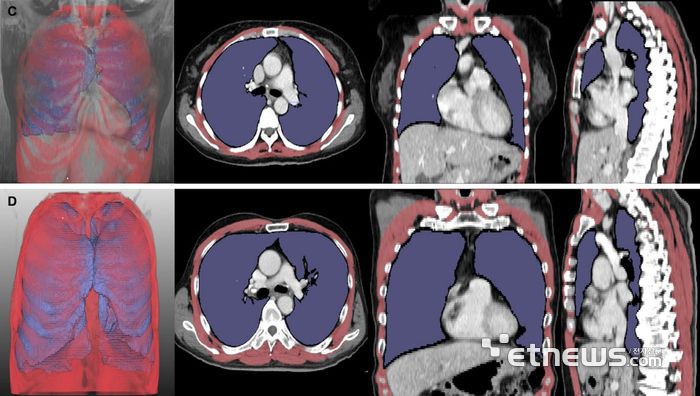

루게릭병 환자의 흉부 CT 분석 결과. 폐 용적 지수(LVI, 보라색)와 호흡근 용적 지수(RMI, 빨간색)가 낮은 환자는 높은 환자보다 생존 기간(위 5개월 vs 아래 43개월)이 짧았다.

연구팀은 이러한 문제를 해결하고자 딥러닝 소프트웨어를 활용해 흉부 CT 영상에서 폐와 호흡근 부피를 수치로 산출(LVI, RMI)하고 이를 분석했다. 루게릭병 환자 261명의 흉부 CT를 분석해 진행됐으며, 폐·호흡근 용적 지수가 병기가 진행될수록 유의미하게 감소하는 것이 확인됐다. 이 지수들이 낮은 환자군은 기관절개술을 받거나 사망에 이르는 시점이 빠른 경향을 보였다.